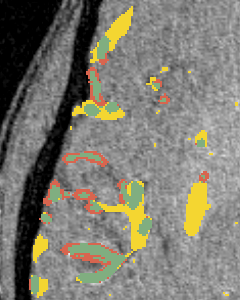

Vessel segmentation is an essential task in many clinical applications. Although supervised methods have achieved state-of-art performance, acquiring expert annotation is laborious and mostly limited for two-dimensional datasets with a small sample size. On the contrary, unsupervised methods rely on handcrafted features to detect tube-like structures such as vessels. However, those methods require complex pipelines involving several hyper-parameters and design choices rendering the procedure sensitive, dataset-specific, and not generalizable. We propose a self-supervised method with a limited number of hyper-parameters that is generalizable across modalities. Our method uses tube-like structure properties, such as connectivity, profile consistency, and bifurcation, to introduce inductive bias into a learning algorithm. To model those properties, we generate a vector field that we refer to as a flow. Our experiments on various public datasets in 2D and 3D show that our method performs better than unsupervised methods while learning useful transferable features from unlabeled data. Unlike generic self-supervised methods, the learned features learn vessel-relevant features that are transferable for supervised approaches, which is essential when the number of annotated data is limited.